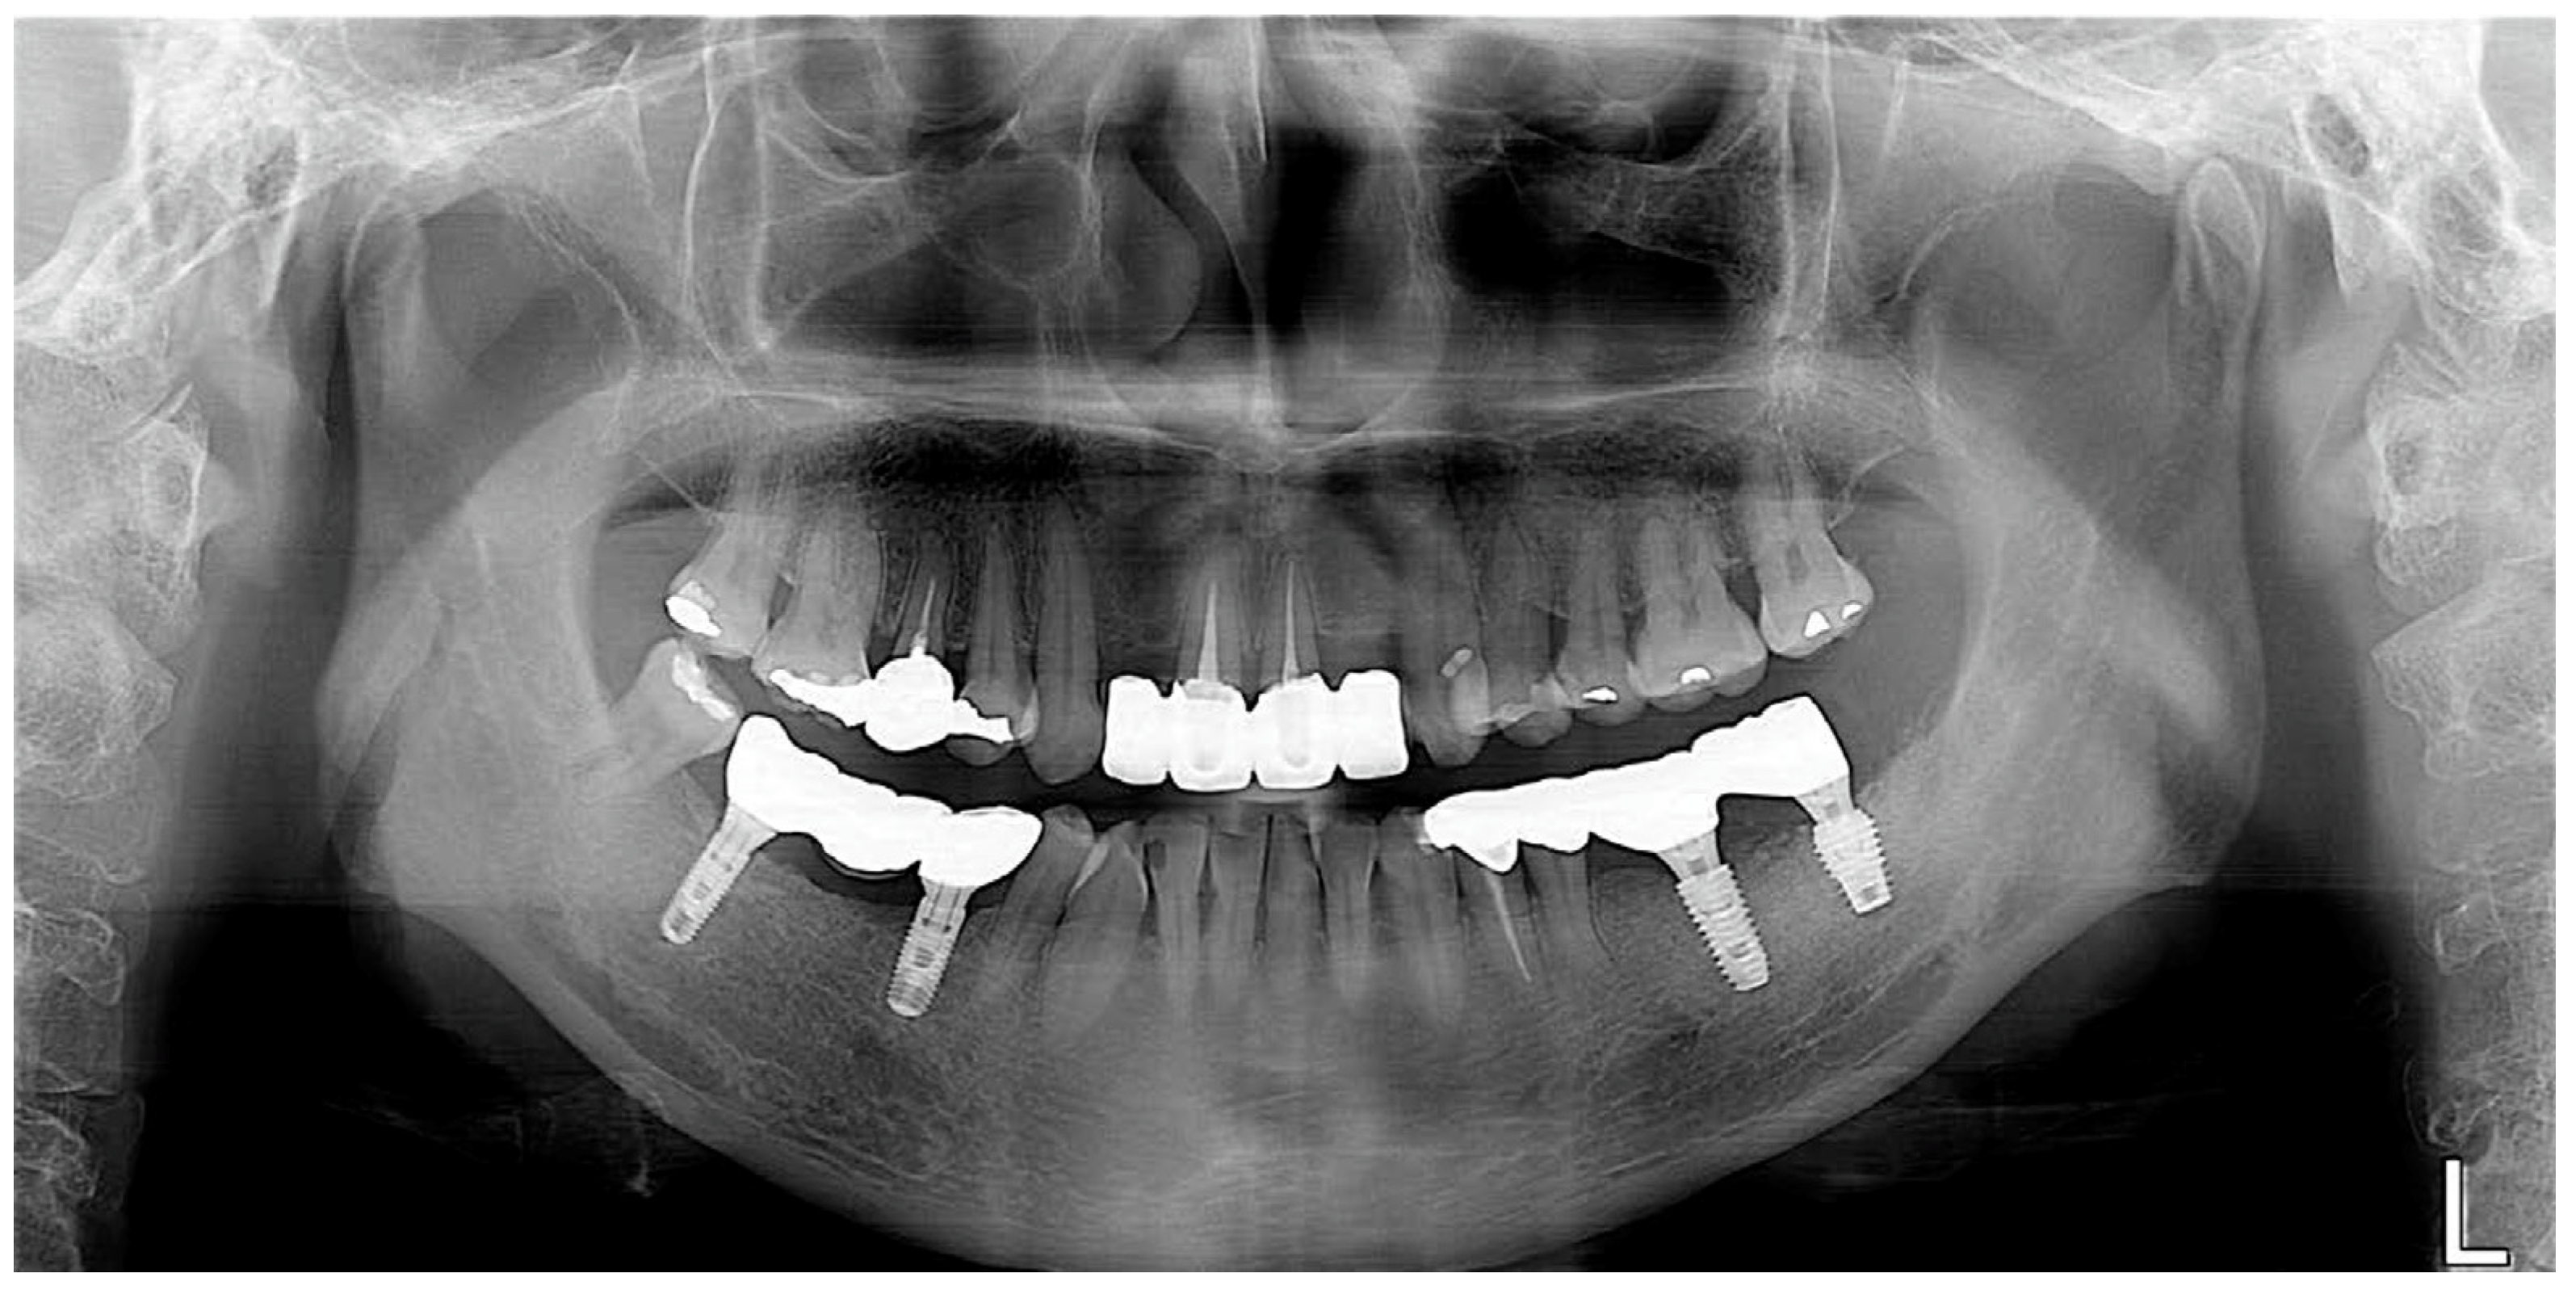

As part of a maintenance therapy program for the patient, a follow-up examination was performed every 6 months and the patient underwent dental plaque control. Additional periodontal treatment was performed when necessary in additional appointments. In addition, panoramic radiographs were taken every year to evaluate the prognosis of the implant. A 3-year follow-up examination showed successful maintenance of the implant prosthesis in the oral cavity (Figure 7).

For this patient, the same periodontal maintenance protocol the patient received in case 1 was performed. Implant prosthesis was successfully maintained at the 3-year follow-up examination (Figure 12).

Figure 7. Panoramic radiograph after 3 years of delivery.

Figure 12. Panoramic radiograph after 3 years of delivery.